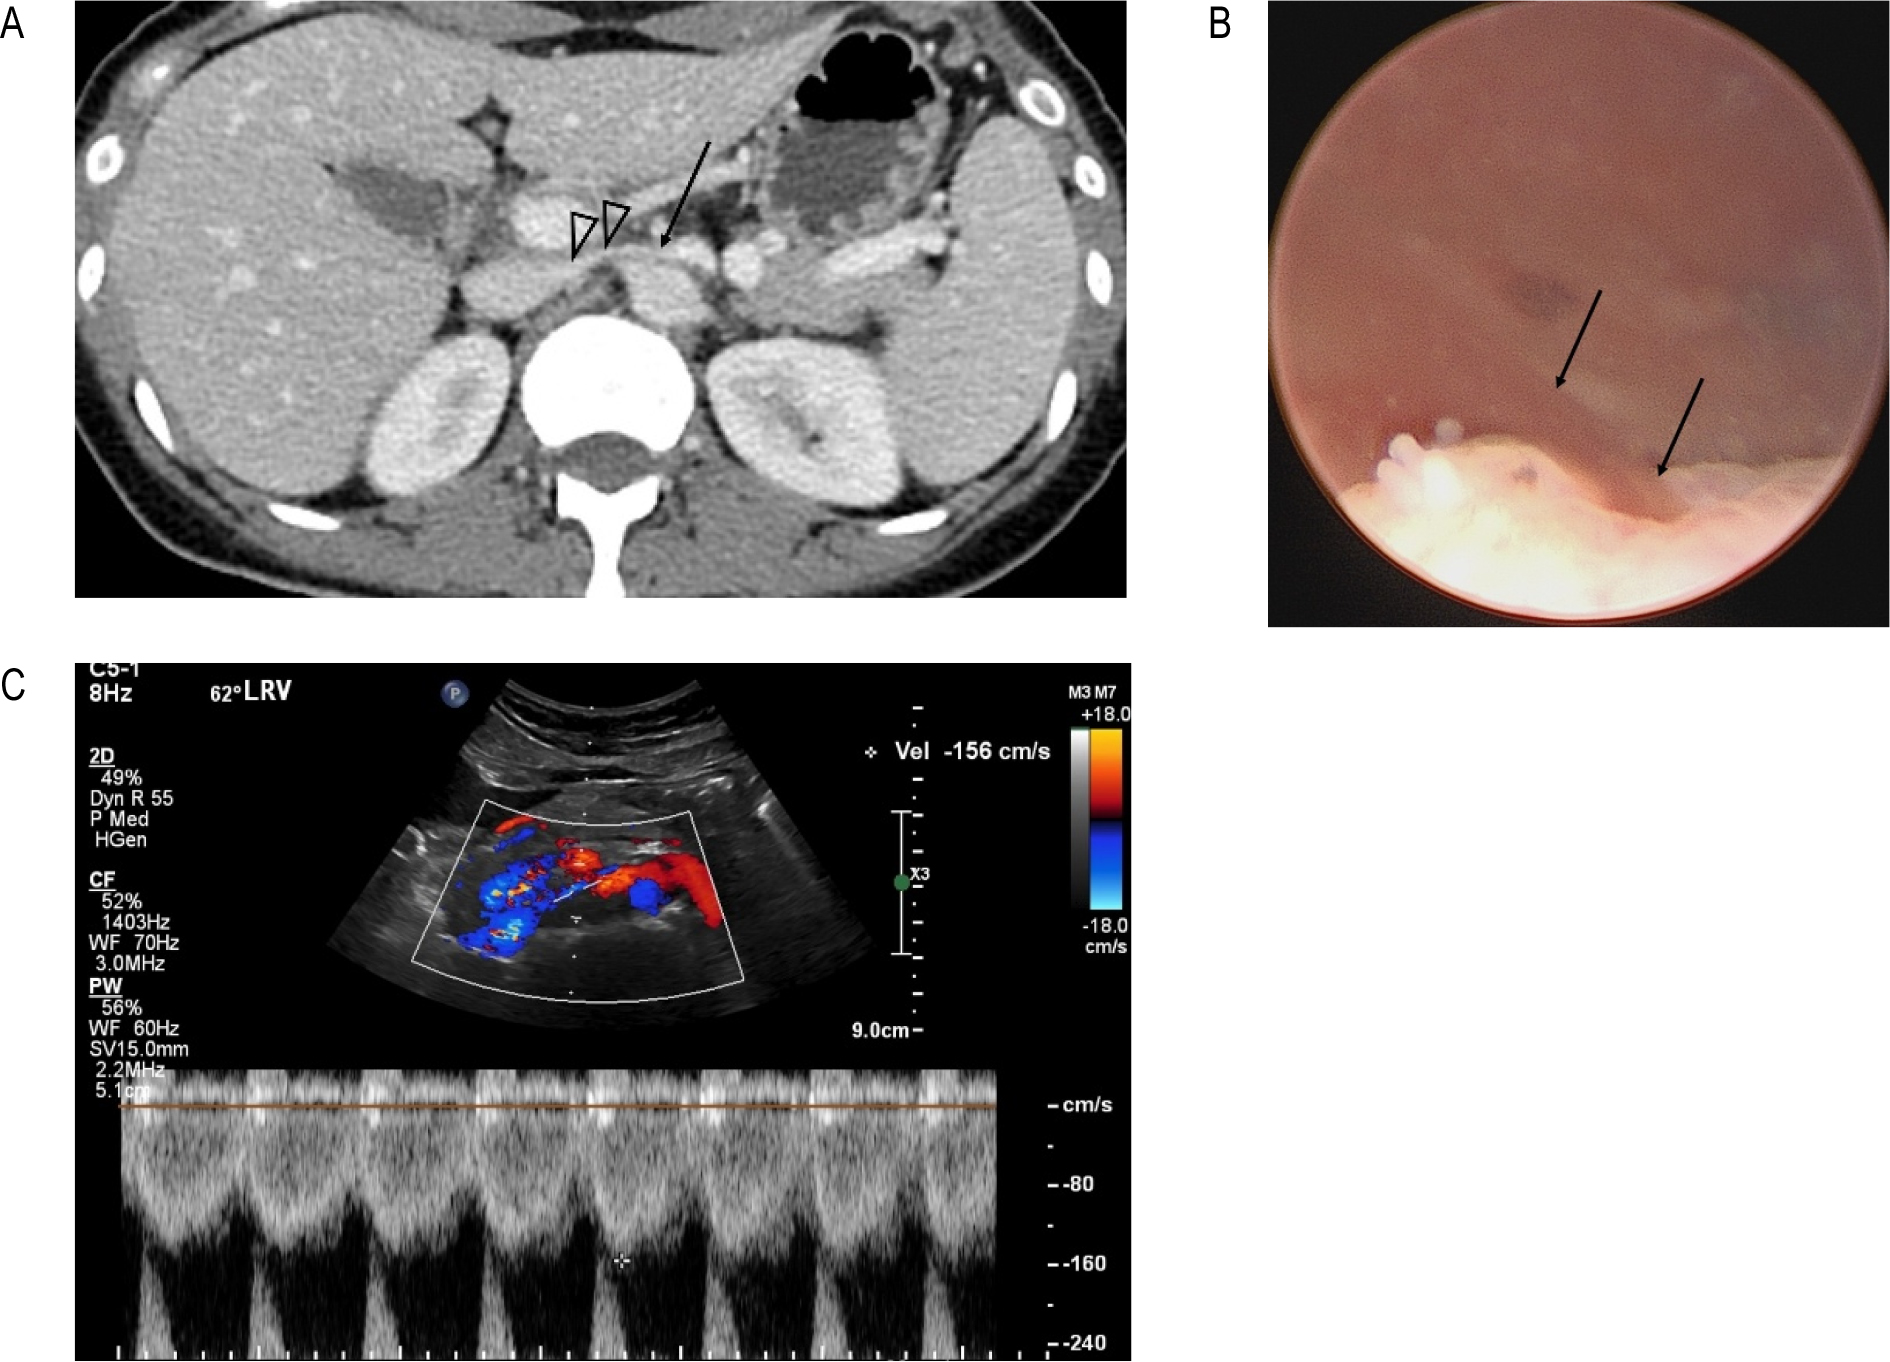

46세 여자로 육안적혈뇨 때문에 CECT검사를 했고 당시에는 특별한 이상소견을 발견하지 못했지만 [그림 3A] 방광경 검사에서 좌측 요관구에서 혈뇨가 나오는 것을 확인했다 [그림 3B]. NCP를 확인하기 위해서 도플러초음파검사를 했으며 AM-LRV의 혈류속도가 156 cm/sec로 NCP를 확인하였다 [그림 3C]. 수면자세에 대한 설명을 듣고 바로 자지 않으려고 노력한 결과 혈뇨는 멎었다. 예정된 유방초음파 검사를 받기위해 15분 정도 반듯이 누워 있었고 검사 후 화장실에 갔을 때 육안적 혈뇨가 다시 생겼다. 이 후 반듯이 눕는 자세는 절대 취하지 않으며 생활했고 이후 15개월 이상 혈뇨가 없는 상태로 지내고 있다.